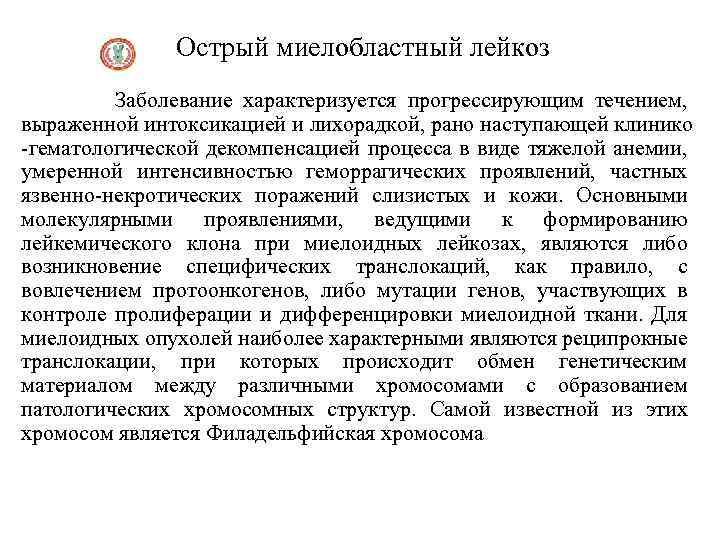

Острый миелобластный лейкоз Заболевание характеризуется прогрессирующим течением, выраженной интоксикацией и лихорадкой, рано наступающей клинико -гематологической декомпенсацией процесса в виде тяжелой анемии, умеренной интенсивностью геморрагических проявлений, частных язвенно-некротических поражений слизистых и кожи. Основными молекулярными проявлениями, ведущими к формированию лейкемического клона при миелоидных лейкозах, являются либо возникновение специфических транслокаций, как правило, с вовлечением протоонкогенов, либо мутации генов, участвующих в контроле пролиферации и дифференцировки миелоидной ткани. Для миелоидных опухолей наиболее характерными являются реципрокные транслокации, при которых происходит обмен генетическим материалом между различными хромосомами с образованием патологических хромосомных структур. Самой известной из этих хромосом является Филадельфийская хромосома